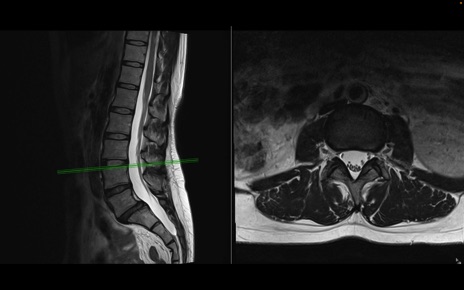

腰椎MRI

T2WI(横断像)

T2WI(矢状断像)